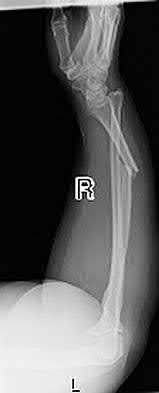

Figure A shows a radiograph of a 19-year-old male with an isolated shotgun injury. On physical examination, he has a 3 cm wound over the posterolateral aspect of his arm. In addition, he has weakness with wrist and finger extension, but no sensory deficits. The patient has received tetanus prophylaxis and antibiotics in the emergency department. What would be the next best steps in treatment?

This patient has sustained a shotgun blast to the midshaft humerus. The next best step would be irrigation and debridement, and external fixation of the fracture.

Shotgun injuries are typically treated as open fractures, whereas low-energy gunshot wounds are treated as closed fractures. The initial operative treatment of shotgun wounds should include irrigation and debridement and stabilization with external fixation. The goal of treatment is to stabilize the severe soft-tissue injury and bone loss, as well as to aggressively debride devitalized tissue and gross contamination.

Figure A shows a high velocity shotgun fracture to the left humerus with retained buck fragments. Illustration A shows a similar injury stabilized with external fixation.